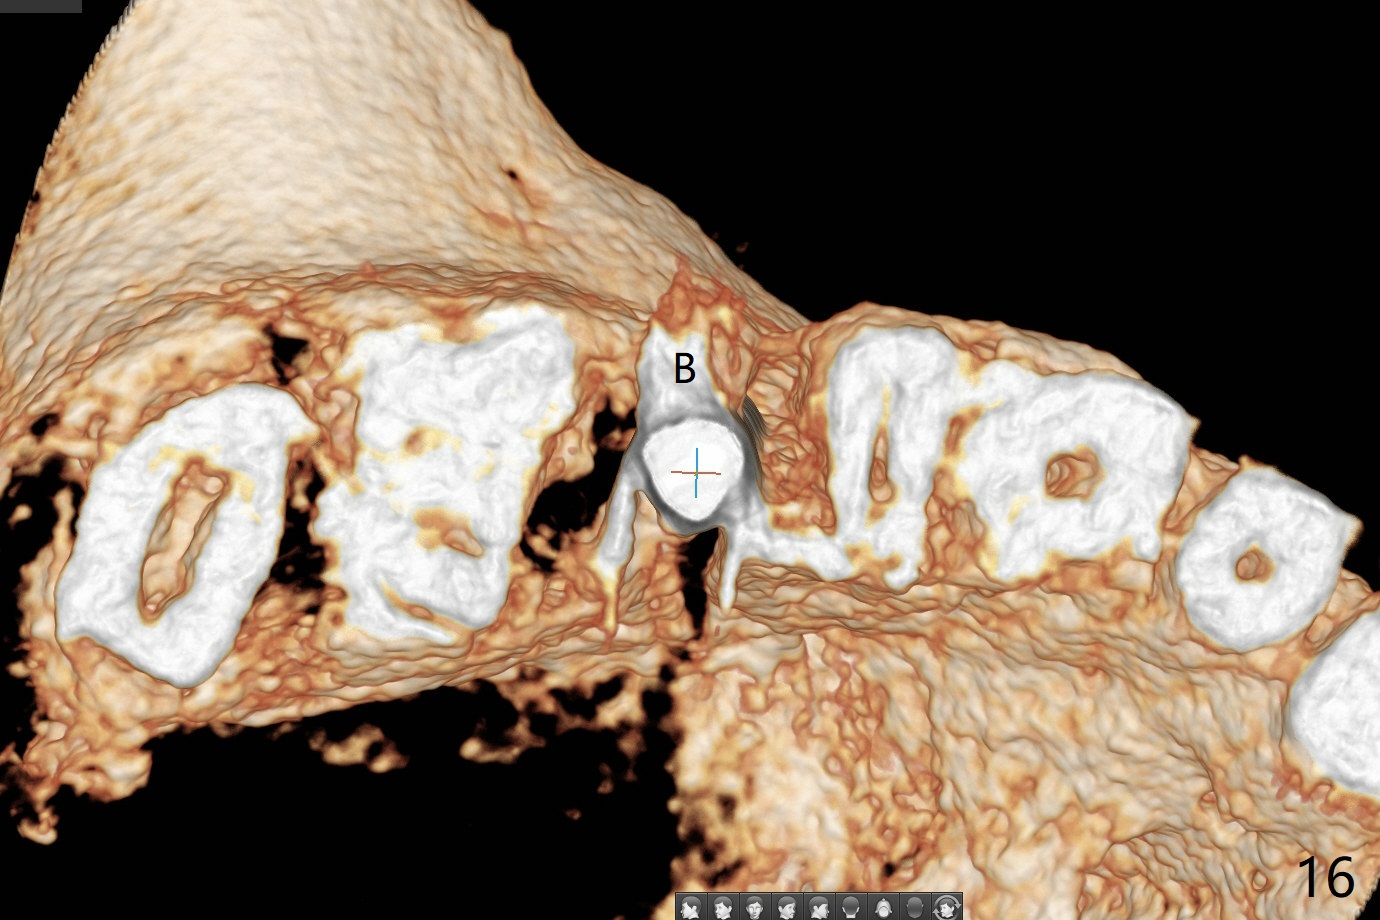

In fact there is a small buccal fistula, which is communicated with the underlying implant threads. Although preop CT shows that the buccal crest is lower than the palatal (3.8x13 mm, Fig.10 P) one, intraop finding of missing buccal plate should dictate a shorter implant (Fig.11) or onlay graft to avoid periimplantitis. Regeneration of the bone plate is limited. Later the fistula disappears with formation of a concavity (Fig.13). There is no symptom. Is bone graft necessary with a remote incision? 3-D images of CT taken 1 year 5 months post cementation show possible mesiobuccal and distopalatal bony defects (Fig.13-16). It is possible that bone graft was placed enough palatal (Fig.16). DO composite at #3 is redo satisfactorily (Fig.17 *).